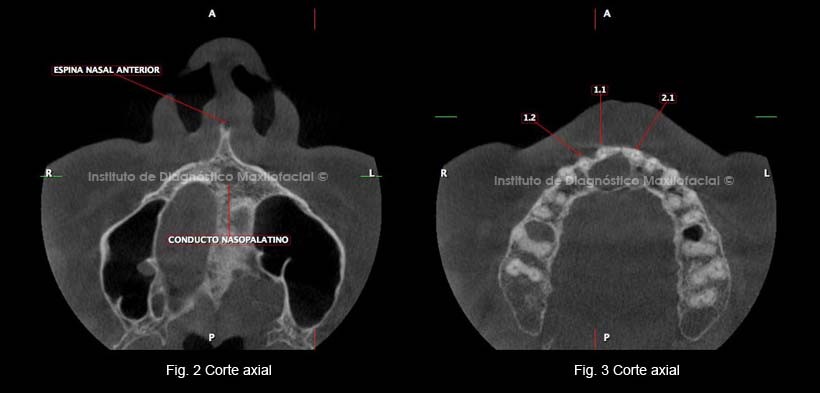

A la evaluación de la tomografía volumétrica (CBCT) en cortes axiales realizados a diferentes niveles, observamos la dilatación del conducto naso palatino como se muestra en el corte a nivel de la espina nasal anterior (figura 2), y en el corte a nivel apical de piezas antero superiores (Figura 3).

En un corte sagital a nivel de la línea media observamos la dilatación del conducto nasopalatino que produce adelgazamiento y erosión de la tabla ósea palatina (Figura 4) , en otro corte sagital vemos la relación con la pieza 1.1. (Figura 5).